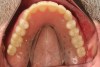

After the implants have been placed, the patient returns for impression procedures and fabrication of the definitive cast. Healing abutments are removed, and definitive stud-style abutments placed (Figure 6). To facilitate technical fabrication procedures of the framework, the clinician places either the housings or a scan body on top of the retentive element prior to impression procedures. An optical scan can be made of the dentition with the housings in place directly using an intraoral scanner (Figure 7). Optical scans of the patient's prosthesis are beneficial; however, it's not critical to fabricating a stud-style overdenture framework as the prosthetic space requirements are not as demanding as bar overdenture restorations.

Fig 6. The patient presents with six existing LOCATOR R-Tx abutments (Zest Dental Solutions) in

place.

Fig 7. Retentive housings are placed and an intraoral optical scan completed.

Figure 7